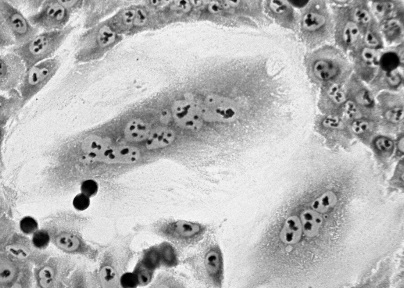

Ученые Института цитологии РАН улучшили коллагеновые структуры, предназначенные для трансплантации клеток

В Институте цитологии РАН (ИНЦ РАН) с помощью перекиси водорода улучшили свойства скаффолдов на ос...